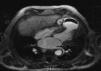

Case reportIn this report, we describe the case of an 82-year-old man, with a previous aortic valve replacement with a bioprosthesis four years previously. He was admitted for anterior STEMI with normal coronary arteries on angiography and apical ballooning. At this time the transthoracic echocardiogram (TTE) revealed a normally functioning aortic prosthesis and the apex was akinetic. He was followed at another institution where, at the first month follow-up visit, he complained of fatigue and dyspnea. TTE showed a VSD and an apical aneurysm of the left ventricle (LV) and the patient was transferred to our institution. In our department a complete TTE displayed a dilated LV, with normal global systolic function and hyperkinesia of the basal and mid segments. A large apical aneurysm was visualized with a LV to right ventricle (RV) turbulent flow suggestive of a shunt with a gradient of 90–97 mmHg (Figure 1). Contrast TTE with Sonovue® (Figure 2) and cardiac magnetic resonance imaging (Figure 3) were performed for further characterization, both showing a large LV apical aneurysm with a thrombus and a VSD with two jets of a turbulent flow to an apical RV pseudoaneurysm, also with a thrombus inside. The patient underwent corrective surgery with a Dor procedure (endoventricular circular patch plasty) combined with VSD closure and resection of the RV pseudoaneurysm (Figure 4). The procedure was successful and the postoperative course was uneventful.